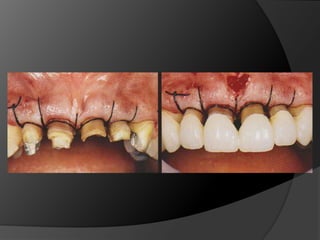

fundamentos de periodoncia en prótesis fijaCuando, por la evolución de lesiones de caries, fracturas, o necesidad de ganancia de retención mecánica en pilares muy cortos, el espacio biológico es violado, existe la necesidad de restablecer sus dimensiones, como una forma de recuperar la salud del periodonto y de facilitar los procedimientos protésicos

fundamentos de periodoncia en prótesis fijaCirugía de Alargamiento CoronalExtrusión OrtodónticaTécnica Combinada

fundamentos de periodonciaen prótesis fijaCuando, por la evolución de lesiones de caries, fracturas, o necesidad de ganancia de retención mecánica en pilares muy cortos, el espacio biológico es violado, existe la necesidad de restablecer sus dimensiones, como una forma de recuperar la salud del periodonto y de facilitar los procedimientos protésicos

fundamentos de periodonciaen prótesis fijaCirugía de Alargamiento CoronalExtrusión OrtodónticaTécnica Combinada